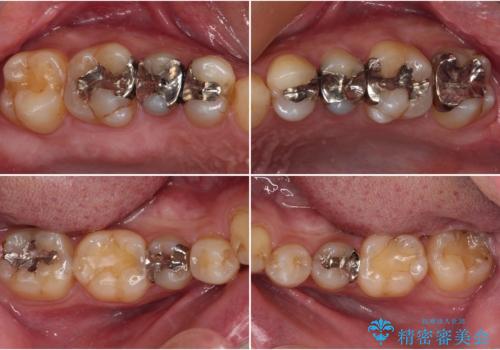

オープンバイトと目立つ銀歯 インビザライン矯正とセラミック修復治療

- 奥歯の目立つ銀歯と上下前歯の叢生と隙間を気にして来院された患者様です。

銀歯については、矯正治療により咬合関係を改善し、矯正治療後半に修復治療を行うこととしました。